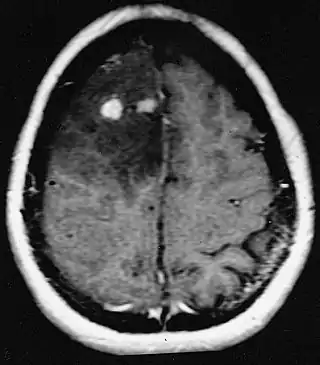

![]() Resonancia magnética de astrocitoma fibrilar difuso con diferentes grados de diferenciación. | ||

Para realizar el diagnóstico el médico puede realizar un examen neurológico o utilizar pruebas de EEG que ayudan a revelar el tamaño, localización y velocidad de desarrollo del tumor. Las tomografías computarizadas y resonancias magnéticas del cerebro pueden mostrar la presencia de una masa difusa que no se ilumina cuando se administra un medio de contraste. En algunos casos, es posible que se requiera una biopsia para confirmar la naturaleza del tumor.[5]